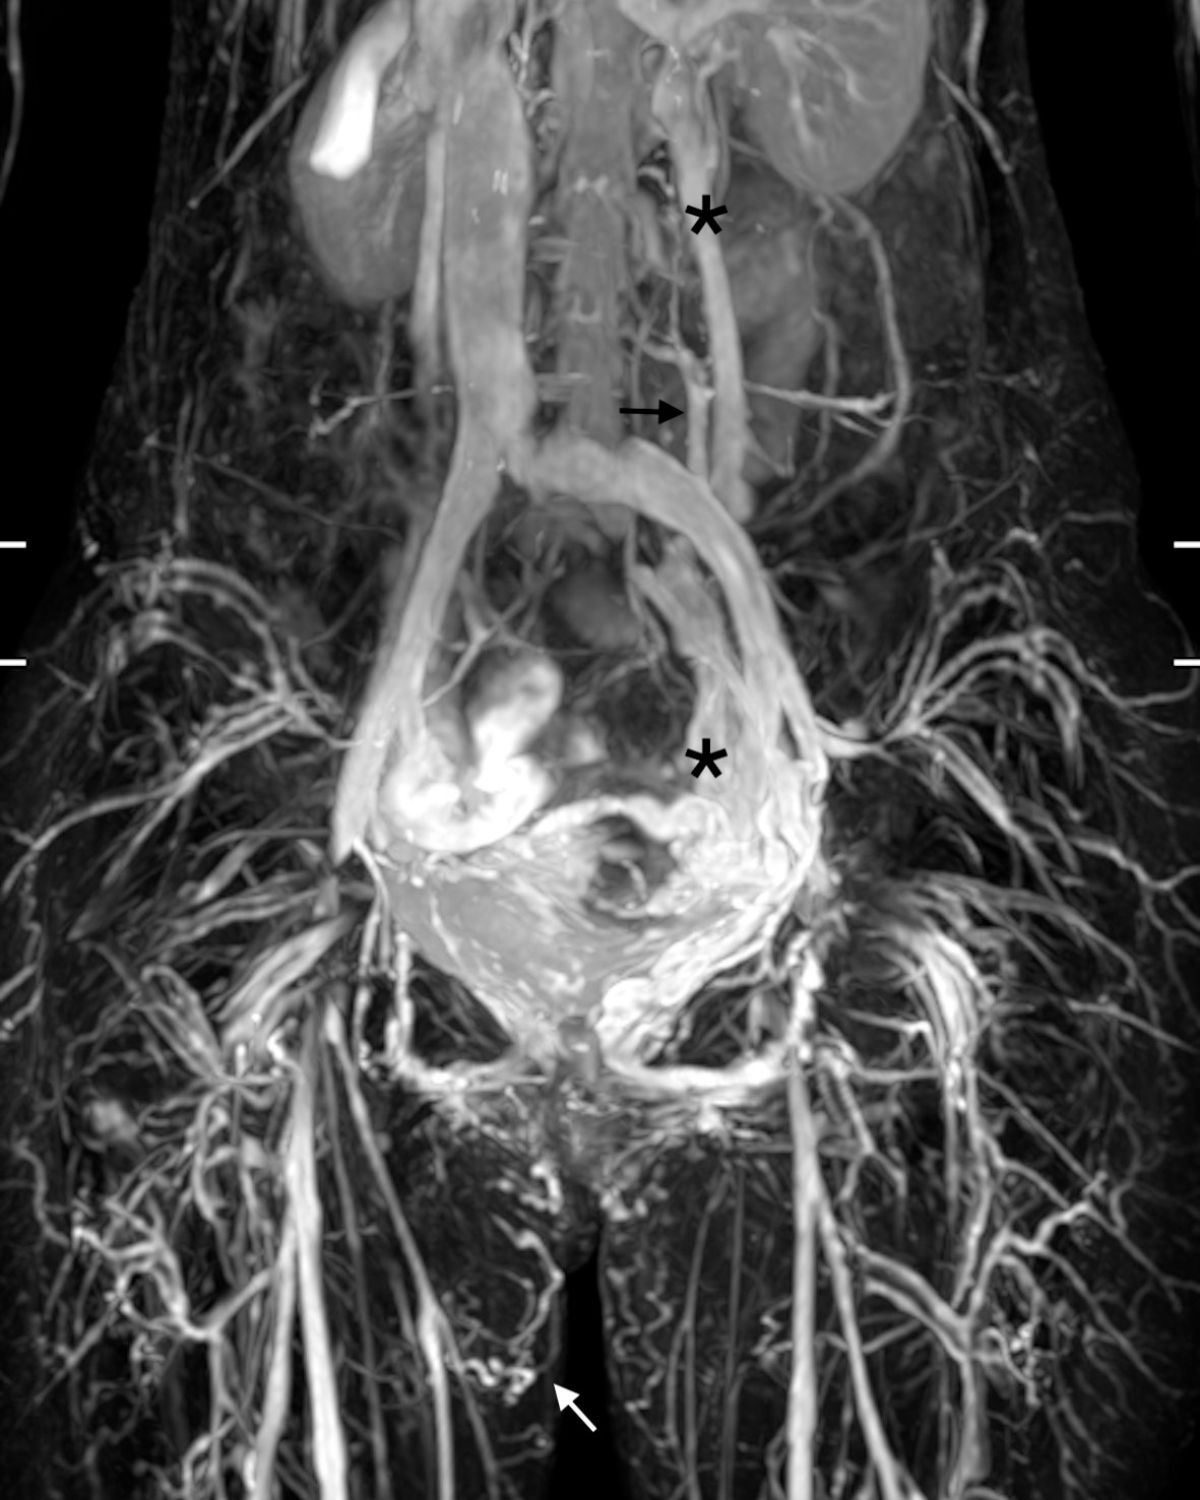

圖三:因為退化的左生殖靜脈 (黑色星號 *)造成過多血流,而使得髂靜脈發生血流過多產生的"相對狹窄",可以看到血流往上升,腰椎靜脈(黑色箭頭)和脊椎方向流去。

過多的血流經過會陰部(Perineal type Pelvic leak),往骨盆腔外滲出(白色箭頭)。

在無毒核磁靜造影中,可以讓病患及醫師視察到逆流及粗大的生殖靜脈及子宮/直腸/膀胱/陰道附近的扭曲的靜脈,甚至在私密處的骨盆腔靜脈滲漏。